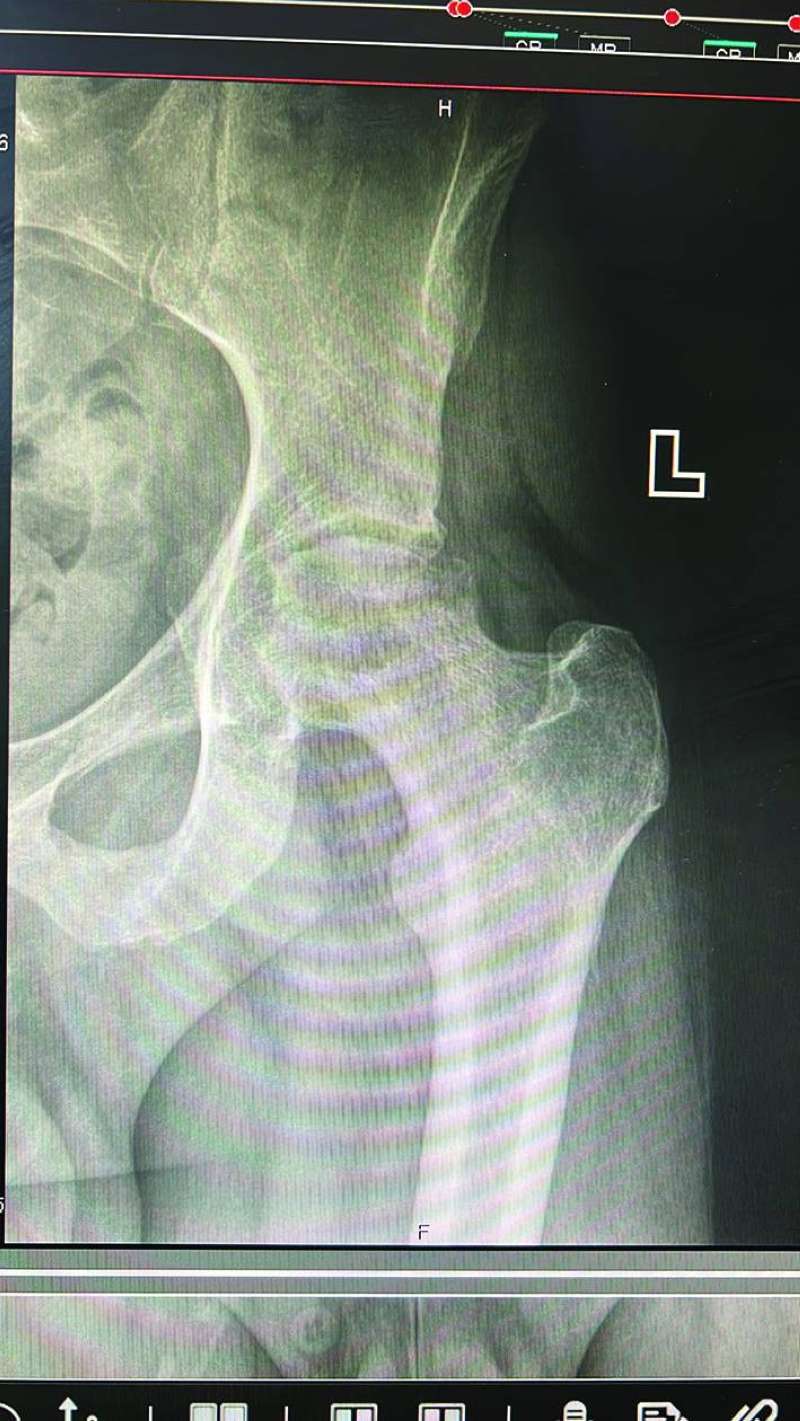

- هي عملية تغيير مفصل الورك لمريض شاب، كان يُعاني من مرض النخر العظمي، الذي يتم فيه فقدان وصول الدم الى مفصل الورك، ما يؤدي الى خشونة شديدة في بعض الحالات، وللأسف هذا ما وصل إليه هذا الشاب الذي عمره 35 سنة، وكما هو معلوم فليس من المتعارف عليه إجراء هذه العملية كعملية يومية، ولكن تحدثنا الى المريض، وكان القرار بإجرائها كعملية يومية، وهذا يحدث لأول مرة في مستشفى المواساة وعلى مستوى الكويت، وحتى على مستوى العالم هناك مراكز محددة تقوم بهذه العملية عبر جراحة اليوم الواحد.